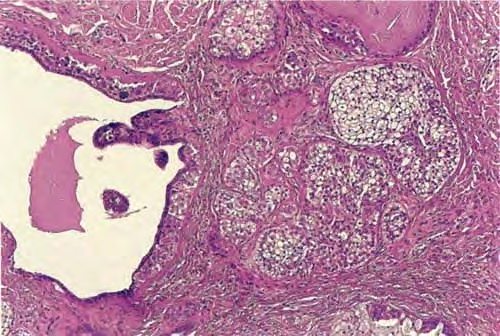

Read MoreNipple duct adenoma = غدووم في قناة الحلمة OLYMPUS DIGITAL CAMERA OLYMPUS DIGITAL CAMERA OLYMPUS DIGITAL CAMERA